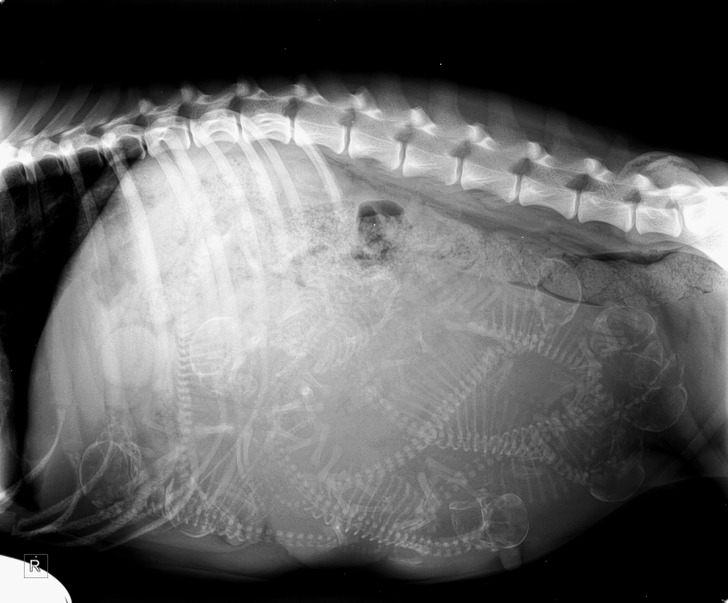

6. The wonders of science - an x-ray of a pregnant dog

Illustration de l'article : 18 photos of unusual physical traits and natural wonders

© eppinizer / Reddit